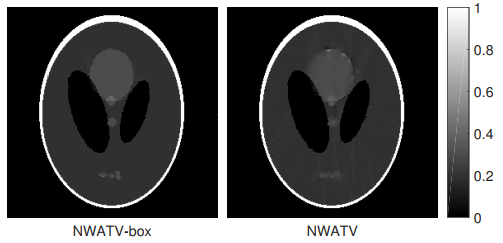

• Sparse-view computed tomography (CT) is an important way to reduce the negative effect of radiation exposure in medical imaging by skipping some X-ray projections. However, due to violating the Nyquist/Shannon sampling criterion, there are severe streaking artifacts in the reconstructed CT images that could mislead diagnosis. Noting the ill-posedness nature of the corresponding inverse problem in a sparse-view CT, minimizing an energy functional composed by an image fidelity term together with properly chosen regularization terms is widely used to reconstruct a medical meaningful attenuation image. In this paper, we propose a regularization, called the box-constrained nonlinear weighted anisotropic total variation (box-constrained NWATV), and minimize the regularization term accompanying the least square fitting using an alternative direction method of multipliers (ADMM) type method. The proposed method is validated through the Shepp-Logan phantom model, alongisde the actual walnut X-ray projections provided by Finnish Inverse Problems Society and the human lung images. The experimental results show that the reconstruction speed of the proposed method is significantly accelerated compared to the existing $ L_1/L_2 $ regularization method. Precisely, the central processing unit (CPU) time is reduced more than 8 times.